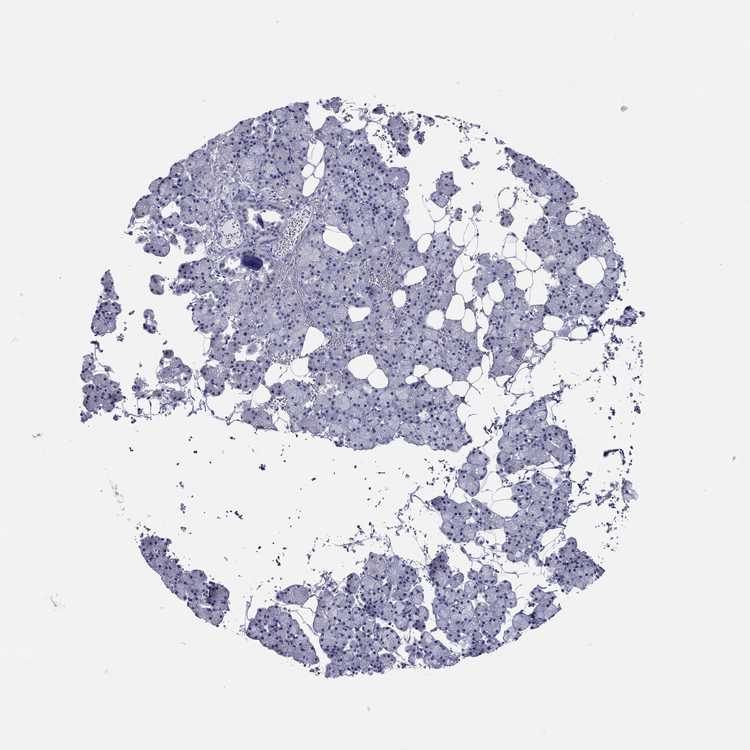

SALIVARY GLAND - Antibody stainingi

Antibody staining in the annotated cell types in the current human tissue is reported as not detected, low, medium, or high, based on conventional immunohistochemistry profiling in selected tissues. This score is based on the combination of the staining intensity and fraction of stained cells.

Each image is clickable and will lead to virtual microscopy that enables deeper exploration of all samples and also displays staining intensity scores, fraction scores and subcellular localization as well as patient and tissue information for each sample.

Antibody HPA036313Antibody HPA052147

Glandular cells Not detectedNot detected